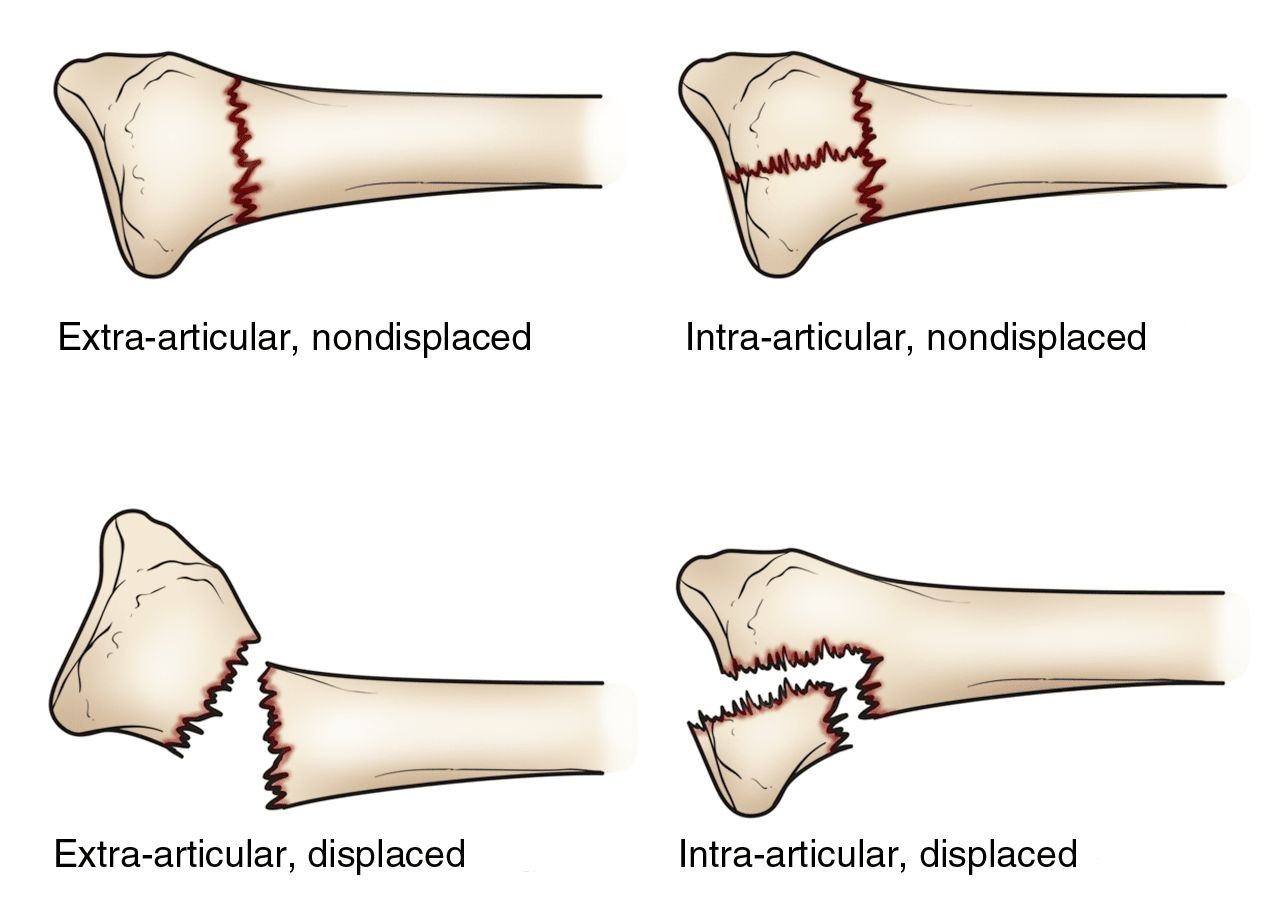

شکستگی هایی با جابجایی زیاد، چند قطعه ای، یا با در رفتگی مفصل مچ دست نیاز به جراحی و زمان بیشتر برای بهبود دارند.

– شکستگی های بدون جابجایی استخوان، یعنی آن هایی که استخوان ها در محل اصلی خود باقی مانده اند، معمولاً با گچ گیری و بیحرکت نگه داشتن مچ دست درمان می شوند. این روش درمان ساده و ارزان است و عوارض جراحی را ندارد. طول زمان لازم برای بهبودی با این روش حدود ۶ هفته است.

– شکستگی های همراه با جابجایی استخوان، یعنی آن هایی که استخوان ها از محل اصلی خود منحرف شده اند، معمولاً نیاز به جراحی دارند تا استخوان ها را تراز کرده و با پلات و پیچ جراحی ثابت نگه دارند. این روش درمان پیچیده و گران است و خطر عفونت، التهاب، خون رسانی نامناسب و عدم تطابق استخوان ها را دارد.